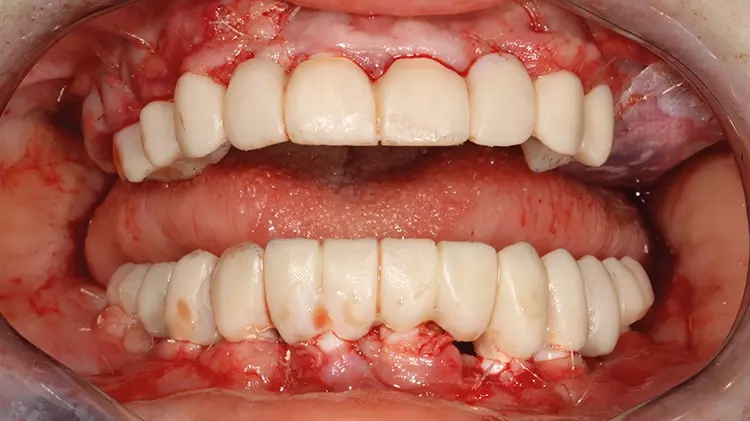

Abb. 16: Z. n. intraoperativer Wiederherstellung von Funktion und Ästhetik mithilfe von laborgefertigten, PMMA-Langzeitprovisorien auf den einteiligen

Implantaten. SDS

Abb. 16: Z. n. intraoperativer Wiederherstellung von Funktion und Ästhetik mithilfe von laborgefertigten, PMMA-Langzeitprovisorien auf den einteiligen Implantaten.

Abb. 17: Z. n. intraoperativer Wiederherstellung von Funktion und Ästhetik mithilfe von laborgefertigten, PMMA-Langzeitprovisorien auf den einteiligen

Abb. 17: Z. n. intraoperativer Wiederherstellung von Funktion und Ästhetik mithilfe von laborgefertigten, PMMA-Langzeitprovisorien auf den einteiligen Implantaten.